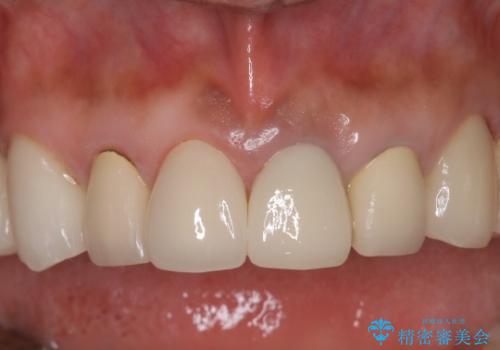

オールセラミッククラウンにすることで、色と形態をきれいにすることができました。